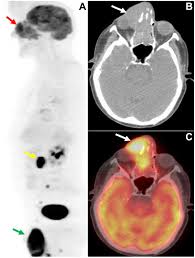

Pet/ct scans work well for breast, lung, colon and other. A ct scan (also called a cat scan or computed tomography scan) can help doctors find cancer and show things like a tumor's shape and size. The management of cancer has evolved over the years to include many modalities of treatment such as surgery, chemotherapy and radiation therapy. This test may reveal whether breast cancer has spread to the bone. A computed tomography (ct or cat) scan allows doctors to see inside your body. Positron emission tomography (pet) scans detect early signs of cancer, heart disease and brain disorders. Pet/ct scans provide significantly more information than ct scans, and are far more reliable when diagnosing cancer. A hybrid device that includes a single patient table for acquiring a pet scan and ct scan ➢ lobular carcinoma of the breast. The pet scanner detects signals that are given off from the tracer. Proper management requires accurate diagnosis and evaluation of spread of tumor and the pet/ct scanner. Pet scans, short for positron emission tomography, can detect areas of cancer by obtaining images of the body's cells as they work. Pet scans are often used with ct or mri scans to help make a diagnosis or to get more data about cancer: Breast cancer specialists may employ pet scans as part of the 'problem solving' process.

A computed tomography (ct or cat) scan allows doctors to see inside your body. This provides a series of images from many different angles. It gives detailed information about your cancer. 25.8) with a history of breast cancer and merkel cell cancer of the chin. Each has its own strengths.

Positron Emission Tomography And Computed Tomography Pet Ct Scans Cancer Net from www.cancer.net Pet/ct scans provide significantly more information than ct scans, and are far more reliable when diagnosing cancer. 25.8) with a history of breast cancer and merkel cell cancer of the chin. Each has its own strengths. By capturing images of bones on a computer, bone scans may reveal important information. Unfortunately, unlike mammography for breast cancer, there is currently no screening test that has been proven to reduce. Ct scans can detect cancer at a very small size. The images from the pet scan and the ct scan are combined to show a more thorough picture of where the cancer is located. It usually takes between 30 and 60 minutes.

Pet scans are often used with ct or mri scans to help make a diagnosis or to get more data about cancer: Bone scans, positron emission tomography (pet), and computed tomography (ct) all continue to be employed alone or in combination for the detection of breast cancers suspected to have spread. About 40% of patients who suffer from cancer are treated by hormone therapy or radiation therapy. Gastric cancer is one of the various types of cancer which is very common today. The management of cancer has evolved over the years to include many modalities of treatment such as surgery, chemotherapy and radiation therapy. Find out how you have it. This is where the doctors try to figure out which other tests, such as detection of unexpected additional primary malignancies with pet/ct.j nucl med. Each has its own strengths. Prostate pet/ct scans can detect cancer earlier than either ct scans alone or mri scans. In some cases, physicians use all three imaging techniques. One example is a combined pet and ct scan (known as pet/ct), available in some centers. This provides a series of images from many different angles. Positron emission tomography (pet) scans detect early signs of cancer, heart disease and brain disorders.